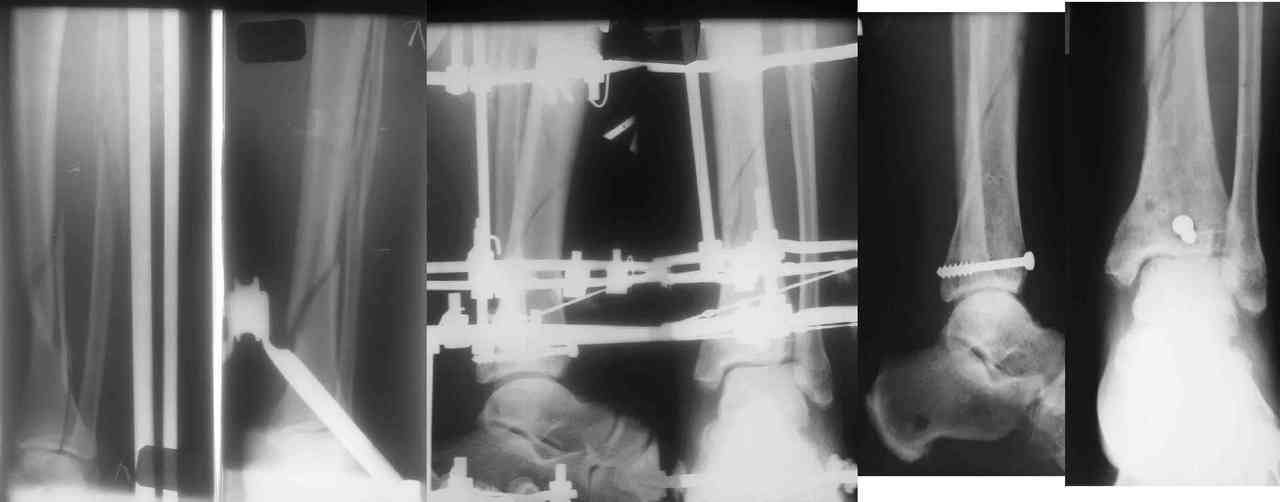

Во вложении - картинки из моей книжки как раз по этой теме

Схемы коррекции различных видов смещения в аппарате

Коррекция длины

Коррекция ротации

Коррекция ширины

В следующих письмах - дополнительные иллюстрации

Открытая репозиция.

Ничто особо не мешает, наоборот - все видно, требования к фиксации не очень высоки - можно просто фиксировать спицей или винтомю Внешний аппарат берет основную нагрузку

Пример -

задний край и диафиз

По поводу конкретного вопрошаемого случая:

1. Скорее всего в аппарате удасться вывести закрыто всё, кроме внутренней лодыжки. Открывайтесь и фиксируйте либо спицей с упором,

либо винтом.

2. ЭОП - очень спорное достижение в таких случаях. Сильные искажения.

Буквально вчера переделывали практически похожий случай. На ЭОПе всё идеально. На пленке - ступенька переднего края. Брали повторно, но уже

пригласили рентгенлаборантку в операционую сделать снимок.

3. Последнее время всё чаще делаем аппарат Илизарова в симбиозе с винтами, которыми фиксируем края (передний и задний), лодыжки и теперь - диафиз.

Позволяет пораньше снять аппарат.